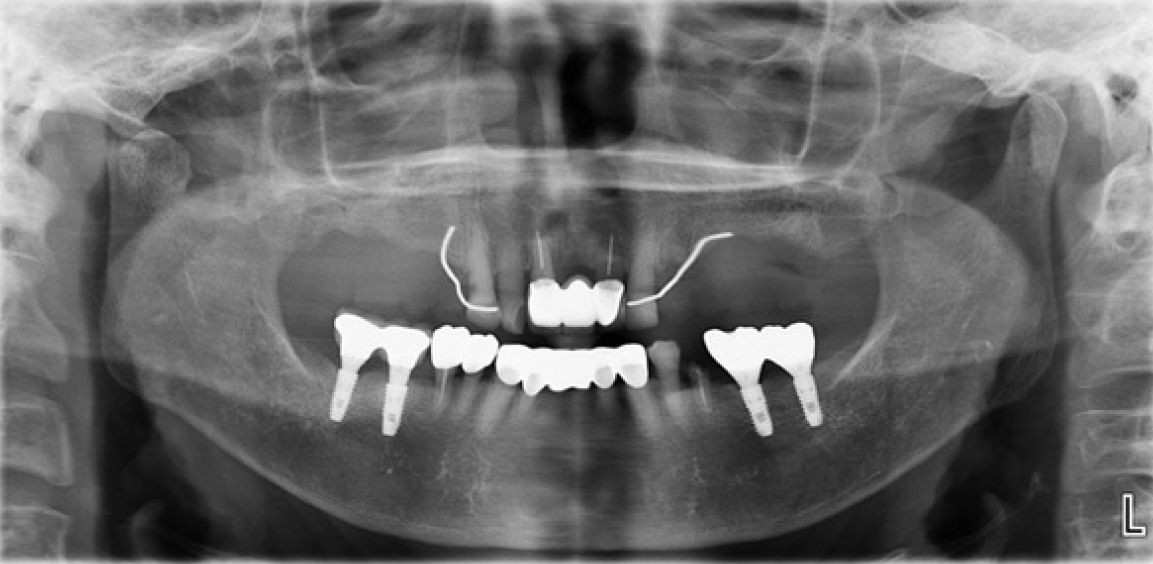

본 증례의 환자는 76세의 여성으로 상악 6전치만 잔존한 상태로 상악 가철성 국소의치의 제작을 위해 내원하였다. 상악은 6전치 중 상악 우측 견치와 좌측 견치의 상태는 동요도 및 파절 상태 없이 양호하였고, 상악 우측 측절치는 총생 상태였으며, 상악 우측 중절치와 상악 좌측 측절치를 이용해 3본 고정성 가공의치 형태로 상악 좌측 중절치의 수복이 되어 있는 상태였고, 상악 잔존 치조제의 상태는 중등도의 흡수 상태가 관찰되었다. 하악은 하악 좌측 제 2소구치는 잔존 치근 상태였다(Fig. 1). 상악의 경우엔 임시의치를 사용중이었고, 잔존 치근 상태인 하악 좌측 제 2소구치는 발거를 진행하였다. 전신병력으로는 B형 간염, 신장 투석, 파킨슨, 당뇨, 고혈압 및 협심증으로 다양한 약을 복용중이었고 비용 및 전신병력의 이유로 임플란트와 같은 수술적인 치료방법의 치료는 어려운 상태였다.상악은 양측 구치부의 결손이 있는 Kennedy Class I 으로 분류하고, 후방 결손부의 수복을 위해서 상악 가철성 국소의치의 제작을 진행하기로 결정하였다. 상악 가철성 국소의치의 디자인은 양측 상악 견치에 후방연장 국소의치의 유지를 위해 설면 레스트와 원심 유도면, 조직 언더컷으로 인해 RPA 클라스프를 설계하였고, 잔존 치아의 개수가 적어 주연결장치는 구개부를 대부분 피개하는 구개판형 연결장치를 설계하였다. 간접 유지의 역할을 위해 추가적인 설면 레스트의 부여를 고려하였으나 양측 측절치에 설면 레스트의 형성은 상악 우측 측절치의 총생 및 상악 좌측 측절치의 기존 보철 수복물로 인해 한계가 있었다(Fig. 2). 의치의 무게로 인한 탈락을 최대한 보완해보고자 금속 구조물의 제작을 코발트-크롬 합금보다는 보다 가벼운 특징을 가진 티타늄 합금(Ti-6Al-4V)을 이용하여 제작하기로 결정하였고, 7년 이내 요양급여를 통한 보험의치 적용을 받은 기록이 있어 비보험 진료로 진행하기로 하였다.해당 수복의 진행을 위해 양측 견치에 설면 레스트 시트를 구강 내 직접 형성 하였고 삽입 철거로를 고려하여 원심면의 치질 성형을 시행하였다(Fig. 2). 이후 개인 트레이를 제작 후 부가중합형 실리콘(Selection-K V.P.S, Shinhung Co., Seoul, Korea)를 이용해 기능인상채득을 시행하였다(Fig. 3). 이후 주모형을 제작하였고 제작된 주모형을 모델 스캐너(DOF Freedom HD, DOF Inc., Seoul, Korea)를 이용해 스캔하여 디지털 데이터를 형성하였다(Fig. 4). 이후 디지털 데이터를 이용하여 CAD 프로그램(3Shape dental system, 3Shape Inc., Copenhagen, Denmark)를 이용하여 금속 구조물을 디자인하였다(Fig. 5). 이후 해당 디자인된 금속 구조물을 선택적 레이저 용융 방식(SLM)의 3D 프린터(David 1.0, Merain Co., Incheon, Korea)를 이용하여 티타늄 합금(Ti-6Al-4V)으로 금속 구조물을 제작하였다. 또한 티타늄 합금과의 무게 비교를 코발트-크롬 재질의 금속 구조물도 티타늄 합금(Ti-6Al-4V)의 금속 구조물 제작에 사용한 동일한 CAD 파일을 이용하여 3D 프린팅을 통해 제작하였다.제작한 티타늄 합금(Ti-6Al-4V)과 코발트-크롬 합금의 금속 구조물의 후처리를 완료 후 주모형에 적합도 확인 및 무게 측정을 시행하였으며, 티타늄 합금(Ti-6Al-4V) 금속 구조물의 무게는 5.6g 이었고, 코발트-크롬 합금의 무게는 9.5g으로 티타늄 합금(Ti-6Al-4V)의 무게가 코발트-크롬 합금보다 41% 정도 더 가벼운 무게를 나타냈다(Fig. 6).제작된 티타늄 합금(Ti-6Al-4V) 금속 구조물의 적합을 환자 구강내에서 확인하였고, 이후 기록상을 제작하여 악간관계 기록을 채득 후 교합기에 부착하여 치아배열을 시행하였으며, 균일하게 중심교합 시 균일한 교합접촉을 이루는지 확인하였다(Fig. 7).